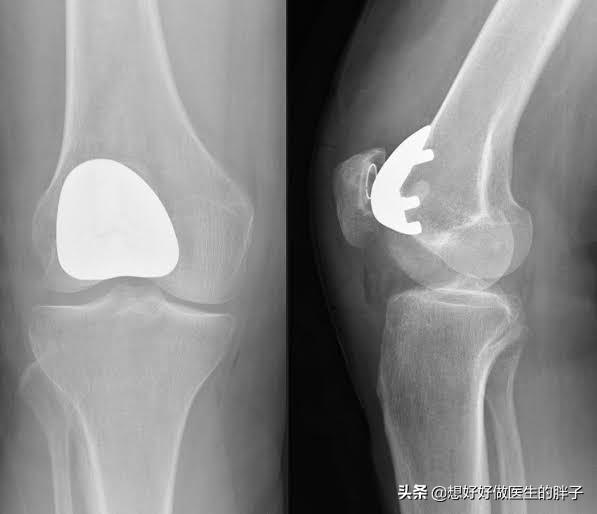

但是在常年的手术经验积累当中,很多医生也发现,部分患者仅仅是内侧的膝关节或者是外侧的膝关节问题比较严重,而针对某一侧的关节问题将整个关节的表面全都置换掉,确实有些可惜。所以目前也开展了单髁置换手术以及模块化的置换手术,我们统称为部分关节置换术。